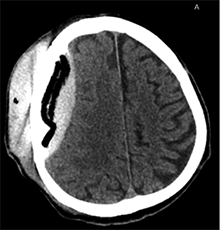

Po 2 savaičių pacientas rastas parkritęs kieme. Buvo matyti kraujuojanti žaizda. Pacientas pakartotinai hospitalizuotas į Neurochirurgijos skyrių. Atlikus GKT, nustatyta 25 mm storio hipodencinė juosta virš dešiniojo smegenų pusrutulio ir 8 mm vidurinių smegenų struktūrų dislokacija (VSD) į kairę (3 pav.). Įtariant lėtinę SDH dešinėje pusėje, pacientas reoperuotas, atliekant rekraniotomiją. Operacijos metu ant kietojo smegenų dangalo (KSD) rasta fibrino, jis pašalintas. Pravėrus KSD, rastas drumstas turinys, nesant aiškių pūlių, ir stora kapsulė. Gausiai praplauta šiltu fiziologiniu tirpalu subduraliai. Kaulinis lopas grąžintas (4 pav.). Po operacijos pacientas pradėjo skųstis stipriu galvos skausmu, tapo vangus. GKT pakartota. Įtarta empiema, nustatyti oro tarpai subduraliai, galvos smegenų VSD – 6 mm. Praėjus 12 dienų po antros operacijos, pacientas operuotas pakartotinai. Operacijos metu atlikta rekraniotomija. Epiduriniame ir subduriniame tarpuose rasta pūlių ir fibrino. Pūliai ir fibrinas pašalinti, paimtas bakteriologinis pasėlis. Žaizda gausiai praplauta šiltu fiziologiniu tirpalu. Kaulinis lopas negrąžintas, minkštieji audiniai susiūti (5 pav.). Po operacijos paciento būklė stabilizavosi. Bakteriologiniame pasėlyje negausiai užaugo E. coli, jautri ampicilinui. Nesant teigiamo efekto gydant ampicilinu, dar 2 savaites pacientui skirta gentamicino. Praėjus 3 savaitėms po trečios operacijos, pacientas perkeltas į slaugos ligoninę palaikomojo gydymo.

3 pav. Prieš antrąją operaciją (25 mm storio hipodencinė juosta virš dešiniojo smegenų pusrutulio, esant 8 mm dislokacijai į kairę; įtarta lėtinė SDH dešinėje)